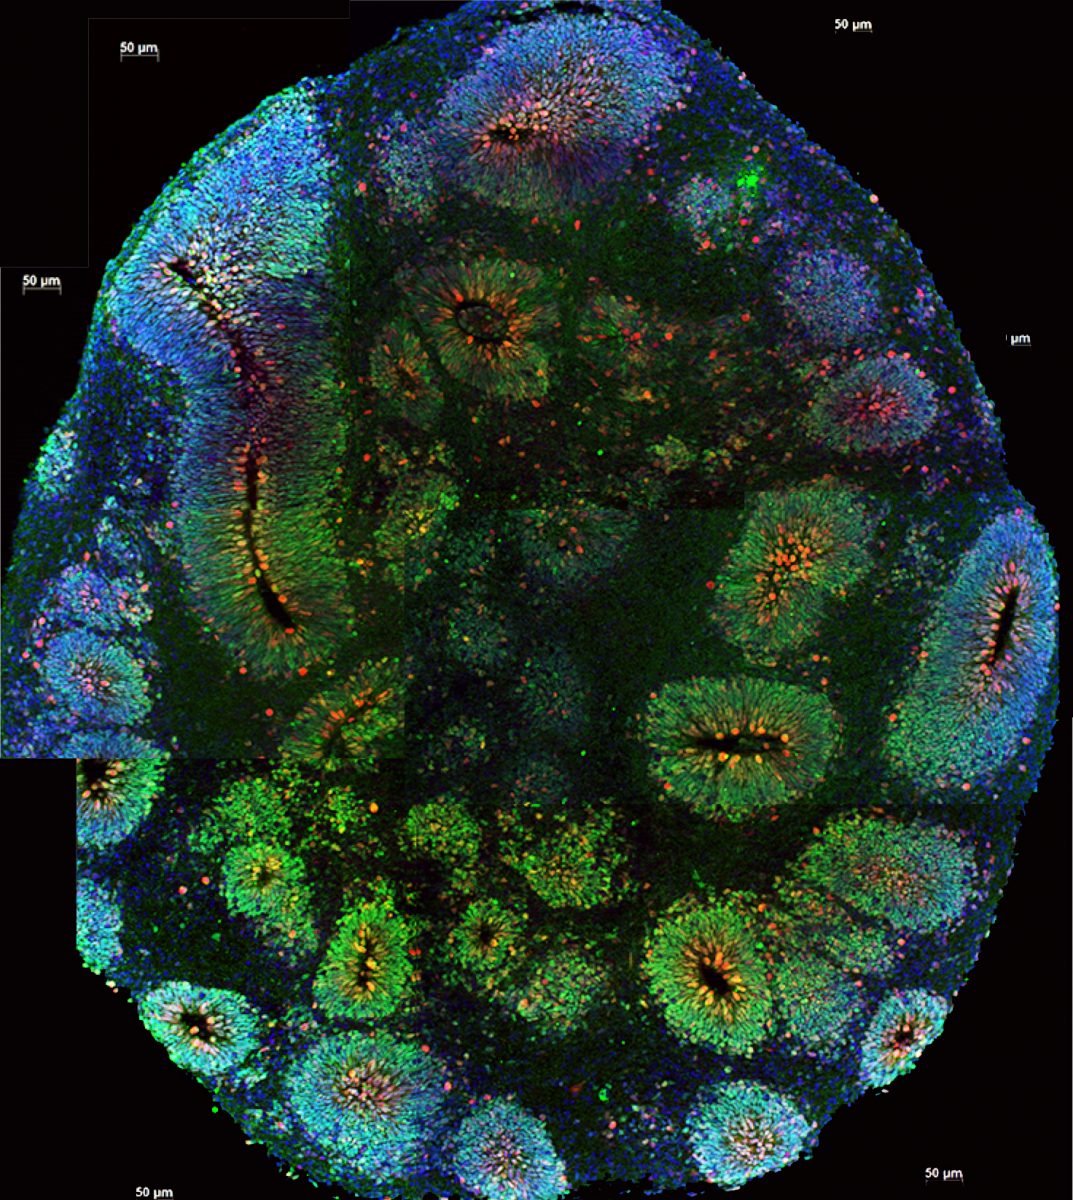

Az agy-organoidok születésétől számított harmincadik napon már megjelennek a szemhez hasonló struktúrák, melyek egy idő után a fényt is érzékelik.

A legújabb kísérletben német, francia és olasz kutatók az organoidokon fejlődő szemhez hasonló struktúrát vizsgálták, az eredmények szerint már a harmincadik napon olyan optikai üregek jelentek meg a sejtcsoporton, szám szerint kettő, amelyek a későbbi fejlődés során többek között lencseszerű sejteket, retina pigmenteket és elektromosan aktív idegi hálózatot is fejlesztettek.

Az indukált pluripotens őssejtekből kialakított mini-agyak szemei fényre is reagáltak és ezt a fényre való érzékenységet mesterségesen is lehetett szabályozni.

A megalkotott 314 organoid 72%-a növesztett ilyen optikai egységeket, és a retina részei a legtöbb esetben interakcióba léptek az agyi sejtekkel, vagyis a valódi szervekhez hasonló működésről tettek tanúbizonyságot. A kutatók szerint in vitro, tehát laboratóriumi körülmények között ilyesmire korábban nem volt példa, ez pedig a vizsgálatok spektrumát nagyban szélesíti, mivel így a szervek közötti együttműködés megfigyelése is lehetővé válik. Ha a miniatűr optikai egységeket sikerül a jelenleginél hosszabb ideig életben tartani, akkor hamarosan már a retina rendellenességek kialakulását és működését is vizsgálhatják a mini-agyakon és szemeken.

(Fotó: Flickr/ nihgov, Elke Gabriel et al/Cell Stem Cell/ Human brain organoids assemble functionally integrated bilateral optic vesicles)